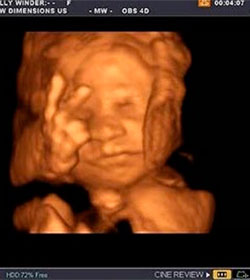

Conferencia Episcopal

“Cambia tu foto de perfil de Facebook por tu ecografía en el vientre

materno”. La campaña por la vida de la Conferencia Episcopal Española para

2013. Vea video

(ReligiónConfidencial 10.04.2013)

Los obispos de la Conferencia Episcopal Española (CEE) han

llamado a todas las personasa cambiar su imagen de perfil de Facebook

por una ecografía de cuando aún se encontraban en el vientre de sus

madres, en el marco de la Campaña por la Vida 2013 que tiene como lema

'Este soy yo. Humano desde el principio' y que ha tenido un coste de

150.000 euros.

No favorecer con el voto programas políticos o leyes contrarias a la fe y a la moral.

Invitan a cambiar la foto del perfil en Facebook por una ecografía en el Día por la Vida 2013

(infoCatólica 08.04.2013)

Los obispos de la Conferencia Episcopal Española (CEE)

invitan a todas las personas, tanto anónimas como públicas, a cambiar su

imagen de perfil de Facebook por una ecografía de cuando aún se encontraban en

el vientre de sus madres, en el marco de la Campaña por la Vida 2013 que tiene

como lema ‘Este soy yo. Humano desde el principio’ y que ha tenido un coste de